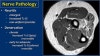

7. Nerves

1) Pathology

This is a nice example of subacute denervation.

Notice on the T1W-image that there is no atrophy. Only edema on the T2W-image.

This was due to proximal radial neuropathy.

- Ulnar nerve

Here we see the ulnar nerve within the cubital tunnel.

The posterior band of the ulnar collateral band forms the floor of the tunnel, while the retinaculum forms the roof.

- Radial nerve

The radial nerve can be best identified at the level of the radial head, where you can see superficial and deep branches in the radial tunnel (arrows). This is a very consistent place to find the radial nerve.

* Arcade of Frohse

The deep radial branches form the posterior interosseus nerve which penetrates the supinator muscle at the arcade of Frohse (arrow).

4) Median nerve

The median nerve goes down behind the Lacertus fibrosis, which is the aponeurosis of the biceps and penetrates the pronator muscle.